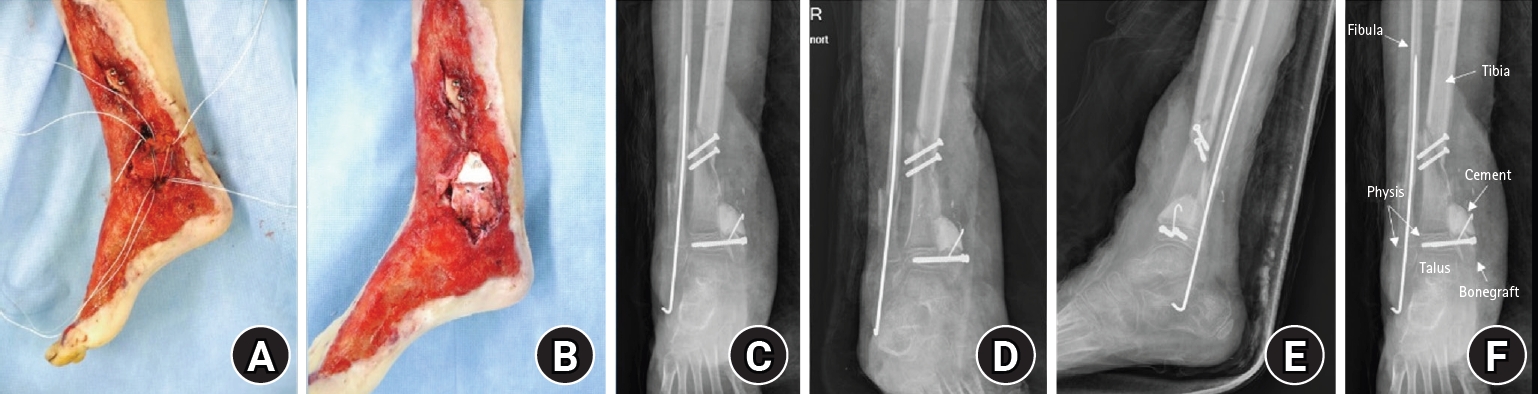

Fig. 4.

Postmedial malleolus reconstruction. (A) Medial clinical photograph obtained after reconstruction of the medial malleolus using an autologous iliac crest bone graft with internal fixation. (B) Medial clinical photograph obtained after reconstruction, showing restoration of the medial malleolar contour and soft-tissue coverage. (C) Anteroposterior postoperative radiograph demonstrating reconstruction of the medial malleolus with internal fixation. (D) Mortise postoperative radiograph demonstrating reconstruction of the medial malleolus with internal fixation. (E) Lateral postoperative radiograph demonstrating reconstruction of the medial malleolus with internal fixation. (F) Anteroposterior radiograph, showing the reconstructed medial malleolus and surrounding anatomical structures.

Stage 2 (definitive reconstruction; August 6, 2016)

The medial malleolar defect (2.5×2.0 cm) was reconstructed using an autologous iliac crest bone graft harvested and contoured to match the defect (Fig. 3) [4,5]. The graft was secured with internal fixation, and postoperative clinical appearance and radiographs confirmed reconstruction and stabilization (Fig. 4). To restore medial ankle stability, harvested gluteal fascia was used as a deltoid ligament substitute and fixed using suture anchors [1]. To mitigate physeal bridging in the residual void adjacent to the injured physis, a bone-cement spacer was placed [4,5]. The extensive soft-tissue defect was covered using ALT flap and skin graft, achieving stable coverage (Fig. 5) [6,7].